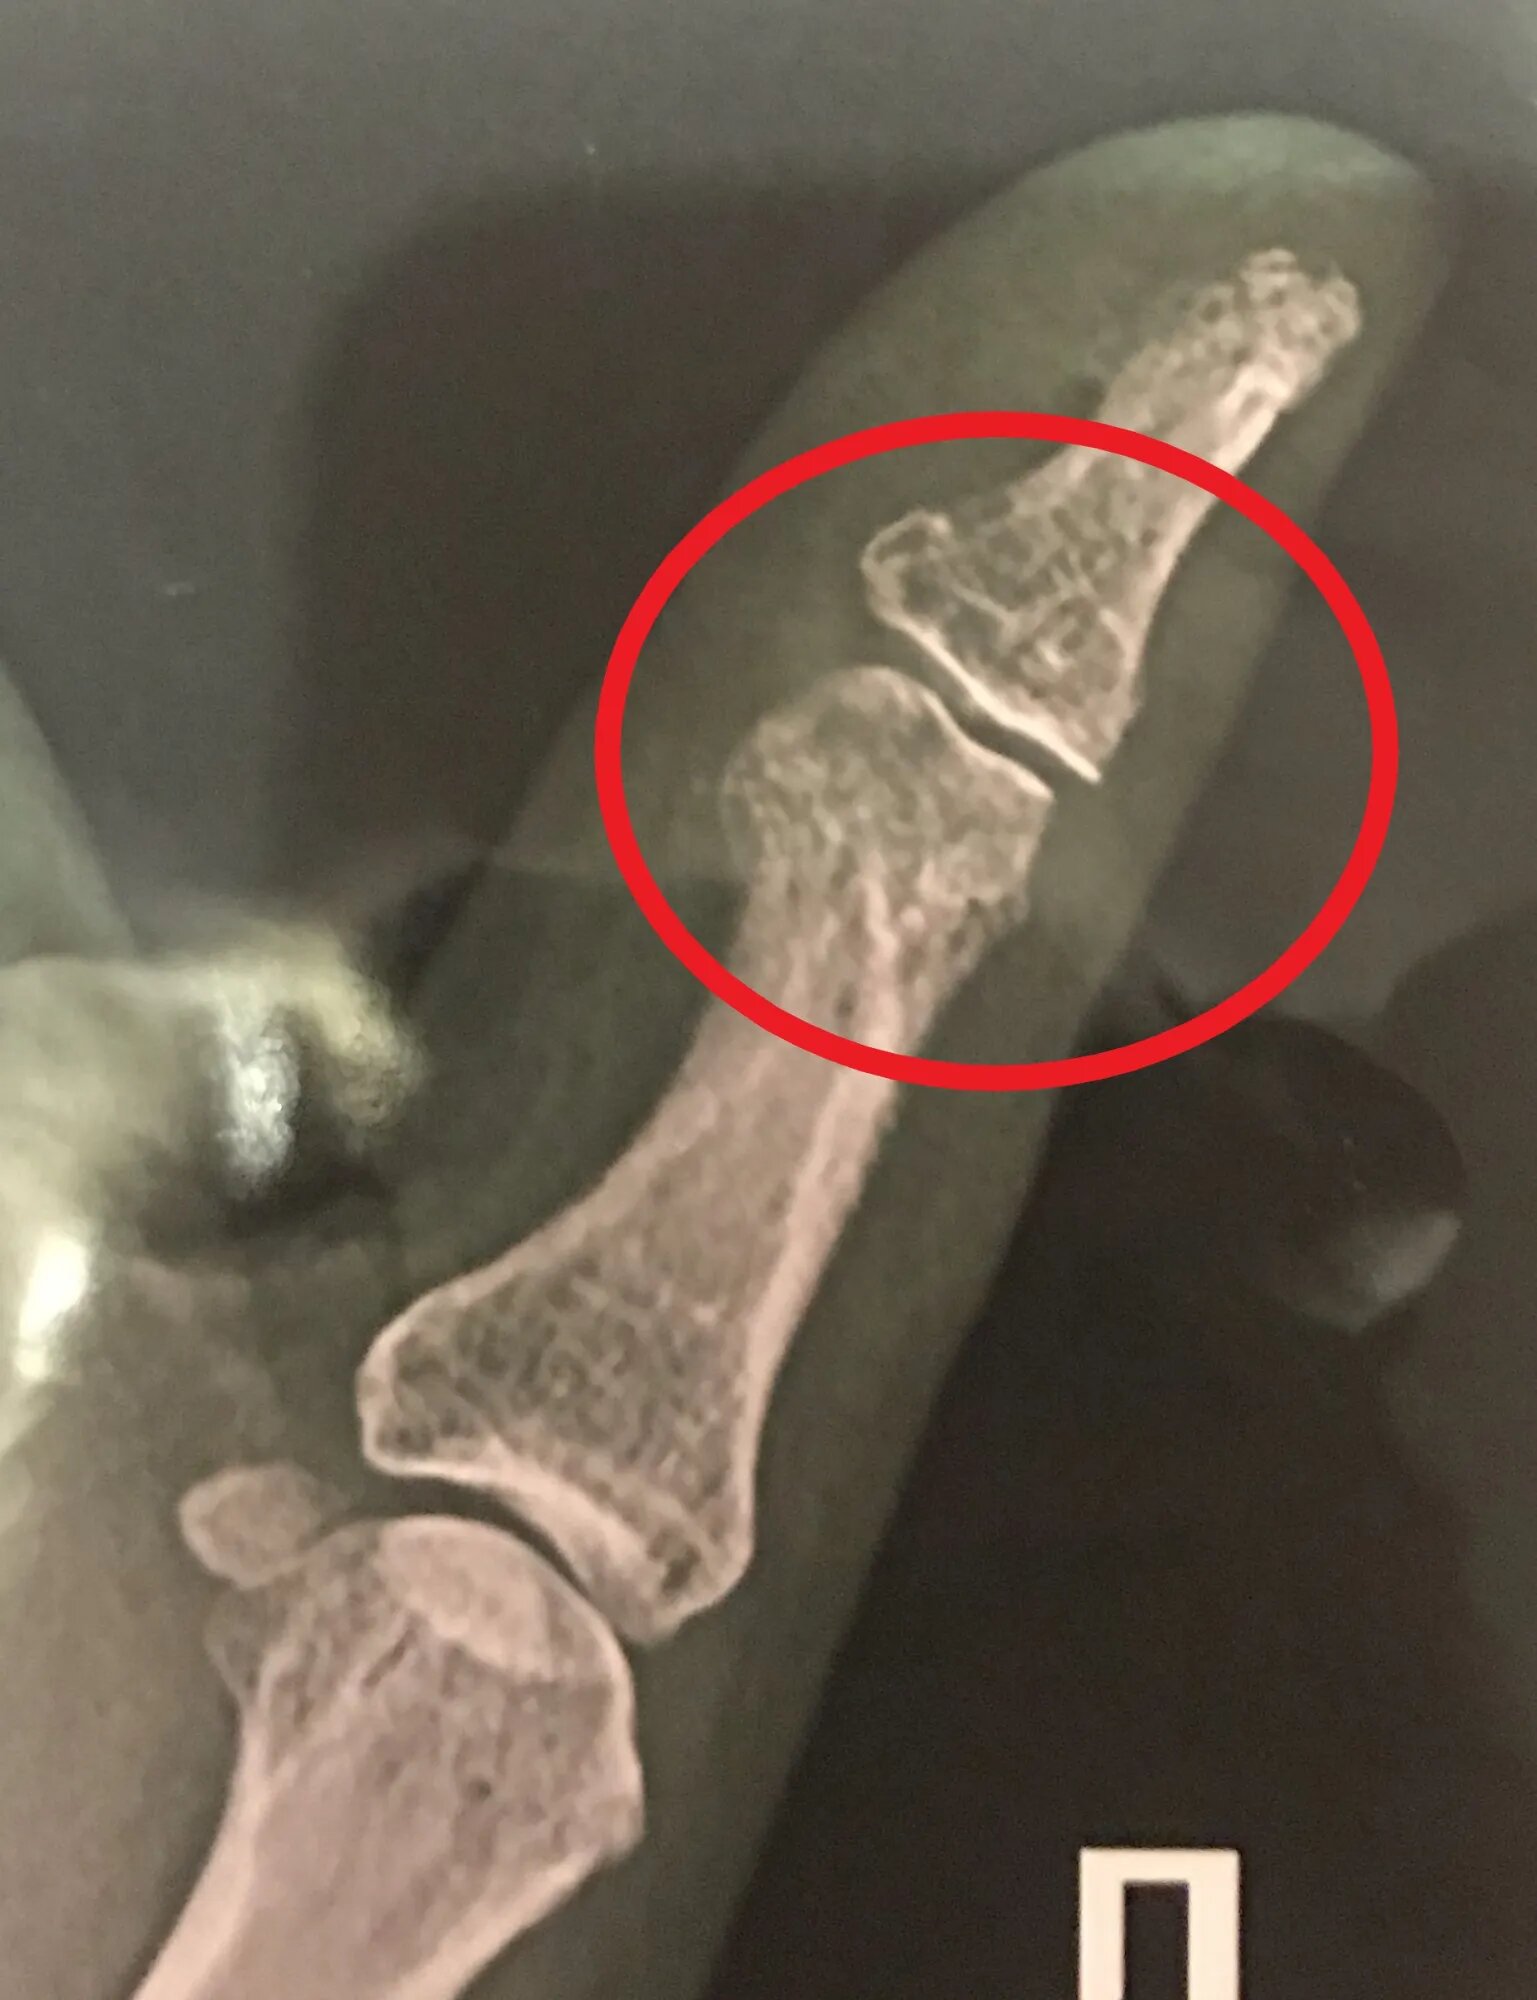

Есть ли воспаление сустава пальца на снимке? Рентген большого пальца кисти в двух проекциях

Здравствуйте. На представленном снимке убедительных данных за патологический процесс нет. Момент воспаления будет более убедительно доказан острофазовыми показателями крови или наличием реакции синовиальной оболочки по данным УЗИ исследования.